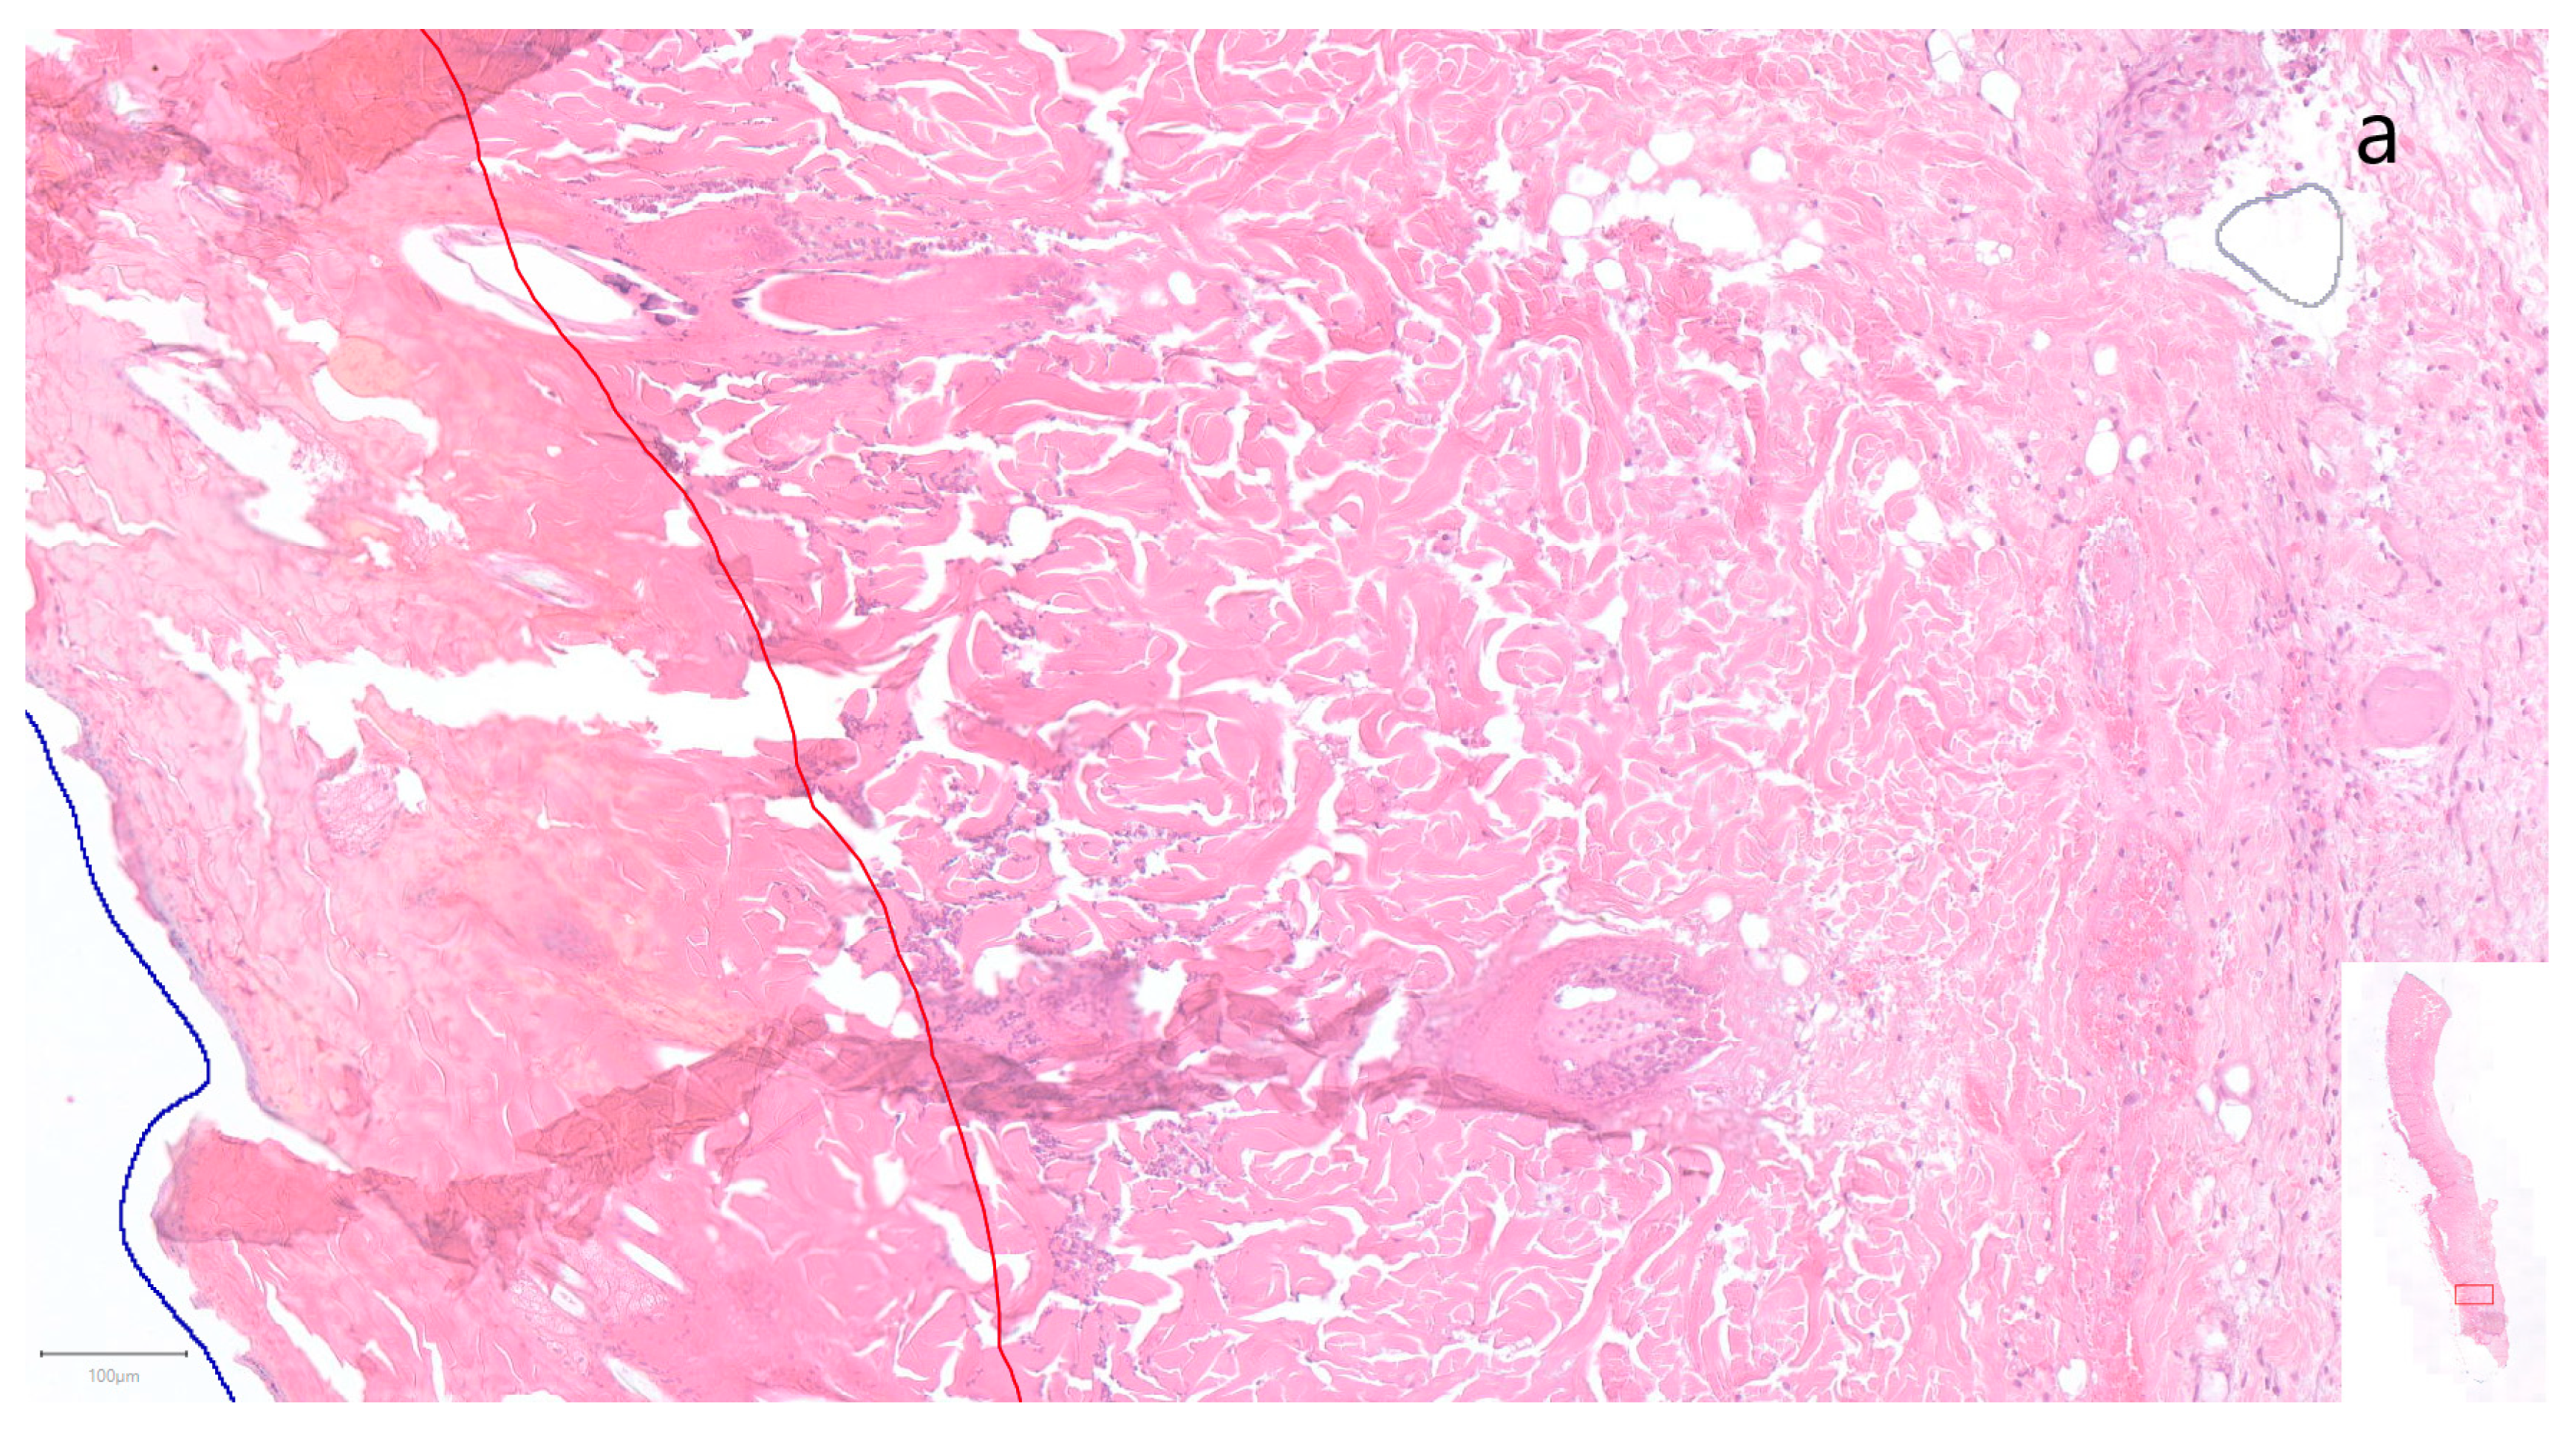

- Müller-Seubert, W.; Ostermaier, P.; Horch, R.E.; Distel, L.; Frey, B.; Cai, A.; Arkudas, A. Intra- and Early Postoperative Evaluation of Malperfused Areas in an Irradiated Random Pattern Skin Flap Model Using Indocyanine Green Angiography and Near-Infrared Reflectance-Based Imaging and Infrared Thermography. J. Pers. Med. 2022, 12, 237. [Google Scholar] [CrossRef] [PubMed]